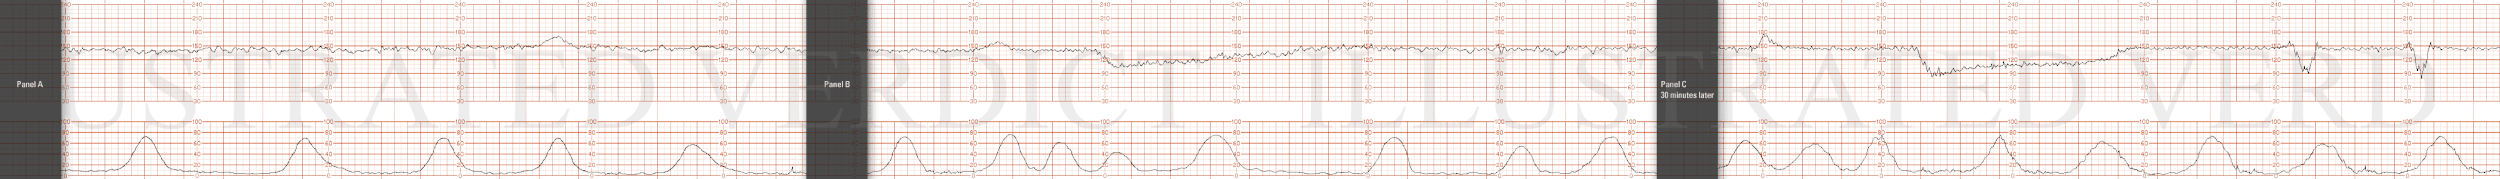

STRIP 78

1. Decelerations are common is all labors but the nature of these

decelerations in the third panel and the marked variability set them apart from the first panel

In the third panel every contraction is producing a decel and each decel is larger and deeper that its preceding one. Give the known natural history of uterine rupture and it propensity for causing rapid deterioration, this deceleration pattern should not be tolerated